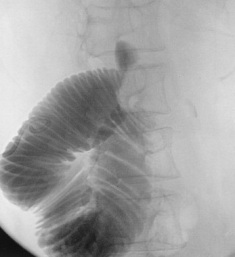

经皮肠造瘘10天后显示Whipple术后的输入袢狭窄

![]() 经皮经空场造瘘行支撑架植入术

ALS处理的外科方法的空肠和空肠吻合术(Jejunojejunostomy)或Roux-en-Y吻合(Roux-en-Y conversion)已经建立[2]。如果不适合进行外科手术也可以进行PTCD或经PTCD十二指肠引流。但是,这两项手术有时可以导致肠内容物经引流导管返流到胆道,引起有生命危险的并发症[4,5]。有两例报告提示直接经皮空肠造瘘安全有效姑息治疗方法,可以缓解肠梗阻和阻塞引起的黄疸[7,8]。本例为经空肠造瘘放置支撑架缓解输入袢综合症的过程。

自膨式金属支撑架已经被用于姑息性治疗恶性胃和十二指肠阻塞[12,13]。目前为止仅有一例报告经皮经肝透视引导下释放支撑架治疗十二指肠狭窄[14]。但是,本例经空肠造瘘释放支撑架,和文献报告一样没有并发症。基于目前商业应用的9F输送器,20mm直径的支撑架经肠途径释放到梗阻输入袢是安全、有效的。